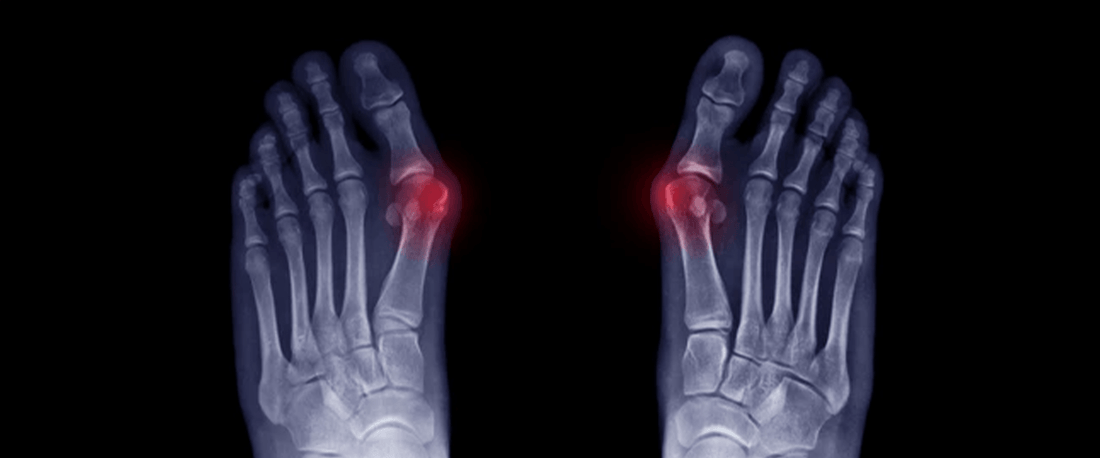

What Are Hammer Toes?

A hammer toe occurs when one or more toes bend abnormally at the middle joint, resembling the shape of a hammer. This can lead to pain, corns, calluses, and difficulty fitting into regular shoes. The condition can be flexible (where the toe can still be straightened) or rigid (where the joint becomes fixed in place).